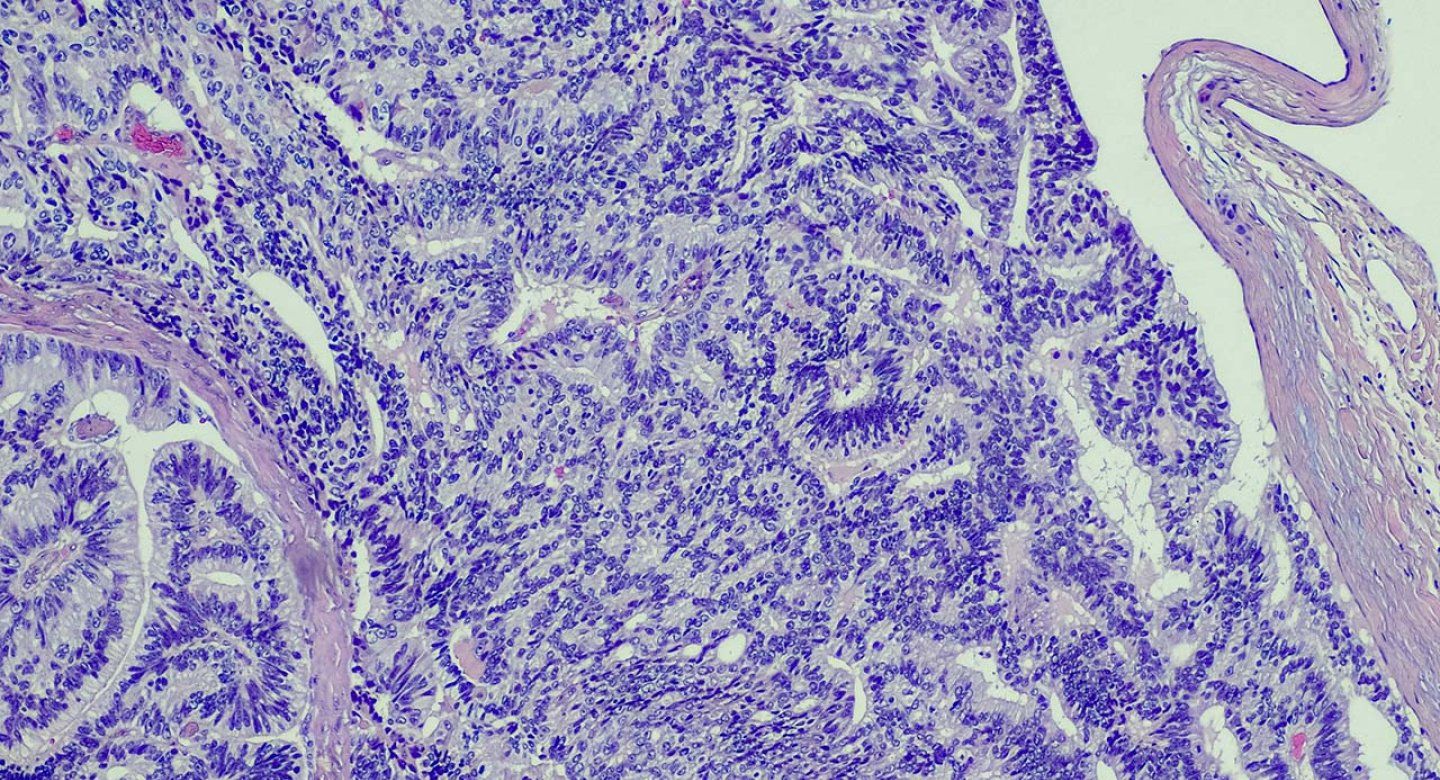

There have been multiple alternatives proposed over the years. The alternative that seems to have the most traction among clinicians and pathologists is “acinar neoplasm,” which describes GG1 as an abnormal growth visible under the microscope, but not one with the potential to spread or kill.